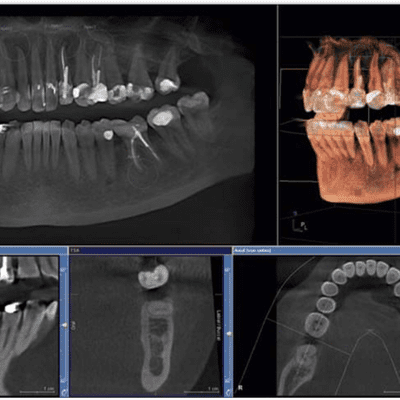

Acerca de Tomografía axial computarizada

El TAC es un metodo image ilógico de diagnóstico que permite observar en el interior del cuerpo.

Tomografía axial computarizada

La tomografía axial es un método imagino lógico de diagnóstico que permite observar al interior de todo el cuerpo.